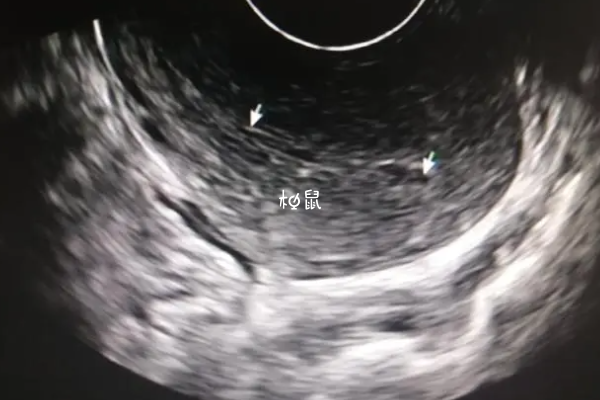

| 月经后14-16天 | 卵泡已经成熟,属于排卵期阶段 | 18-25mm |

正常女性卵泡生长速度在每天1.5-2.0mm左右,在月经结束以后,卵泡大小大约在5-6mm之间,随着月经周期推移,卵泡逐渐生长,在排卵期卵泡的直径可能会达到18-20mm左右,称为成熟卵泡,就可能随时破裂排出卵子。